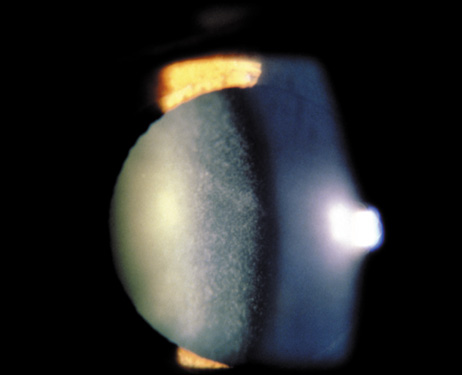

Sunflower cataract is named after the patel-shaped alignment of tiny anterior subcapsular copper deposits. It is a rare manifestation of Wilson's disease (Fig. 5) and is present in 20% to 30% of patients with ocular manifestations. The copper-red to blue-green deposits form a disk-shaped central opacity in the anterior lens capsule, which is usually denser in the pupillary opening, with spoke-like radiations toward the periphery. Posterior lens capsule deposits appear in a fern-like pattern.19 The lens opacities may reverse on a low copper diet and treatment with systemic D-penicillamine.20

Fig. 5. Sunflower cataract. Copper-red to blue-green deposits in the area of the pupil form a disk-shaped central opacity with patel-shaped spoke-like radiations toward the periphery in a patient with Wilson's disease.